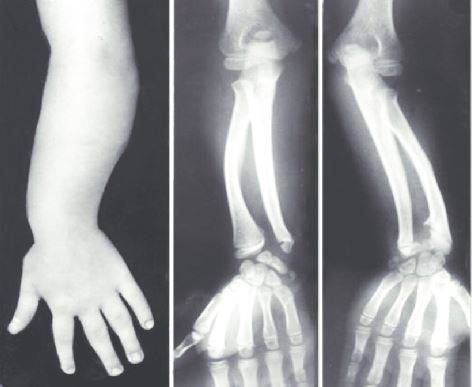

레리-웨일 증후군의 가장 흔한 증상은 중간지절 형성부전이다. 환자들은 사지의 중간 부분, 즉 종아리와 팔뚝이 다른 부분에 비해 상대적으로 짧은 특징을 보인다. 손목에 마데렁 변형(Madelung’s deformity)이 나타나기도 한다. 손목은 두 개의 뼈인 요골(아래팔 바깥쪽에 있는 뼈)과 척골(새끼손가락 쪽 뼈)로 이루어져 있다. 마데렁 변형은 요골 원위 골단이 제대로 성장하지 못하거나 비대칭으로 성장해 요골 원위 관절면이 짧아지는 것을 말한다. 손등 쪽이나 손목의 척골 쪽 변형을 의미하기도 한다. 특히 환자들은 척골이 짧아지거나 부분적으로 탈구될 수 있으며, 요골 변형으로 인해 수근골(손목뼈)이 쐐기 모양으로 변할 수 있다. 손목 주위 뼈에서 변형이 발생하면 손목 관절 통증을 겪기 쉽다. 운동 범위도 감소해 손목을 움직일 때 어려움을 겪는다.

레리-웨일 증후군은 ▲중간지절 형성부전 ▲마데렁 변형 ▲SHOX 유전자 검사를 통해 진단할 수 있다. 레리-웨일 증후군은 아직 완치법이 없다. 환자들은 각 증상에 필요한 치료를 진행하면 된다. 저신장의 경우엔 성장호르몬 치료를 시행할 수 있다. 어린 환자의 경우 변형의 빠른 진행을 늦추기 위해 손목 부위에 석고 부목을 고정시키거나 약물치료를 시도하기도 한다. 청소년기가 지나면서 골격 성장이 거의 끝나면 절골술을 통해 뼈 변형을 고치는 치료를 진행할 수 있다.